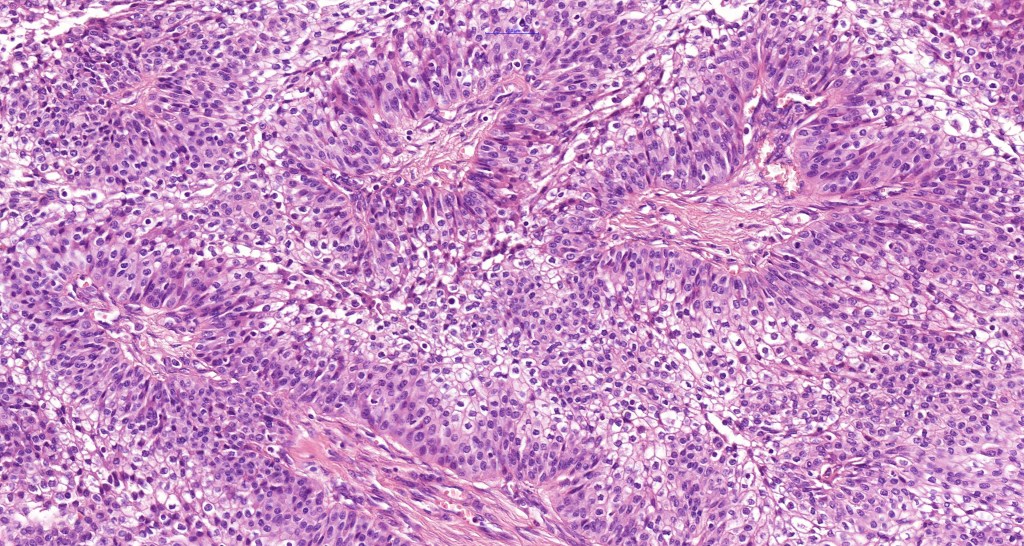

Histological features

•Solid or cystic sharply defined nodule in dermis sometimes extending into subcutaneous fat

•Generally composed of an admixture of small eosinophilic cells & glycogen-rich larger clear cells

•Round to oval vesicular nuclei with small nucleoli or hyperchromatic nuclei

•No pleomorphism & scanty or no mitoses

•Ductal and glandular differentiation

•Squamous differentiation